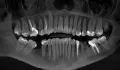

Мне 21 год, вот такие проблемы с зубами, все очень запущенно.

Подскажите, что делать с гнилыми? Я их давно уже не чувствую, если удалить, то как именно? И хочется узнать примерный план действий и стоимость.

Не так все страшно, как Вы расписали. Справа зубы необходимо удалить и поставить имплантаты. С левой стороны зубы необходимо восстановить.